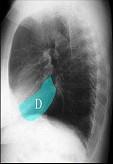

如图所示正常胸部X线影像图像上,该英文字母所代表的肺段为 ( )A.尖段B.后段C.尖后段D.舌叶上段E.舌叶下段

问题 如图所示正常胸部X线影像图像上,该英文字母所代表的肺段为 ( )

选项 A.尖段 B.后段 C.尖后段 D.舌叶上段 E.舌叶下段

答案 E